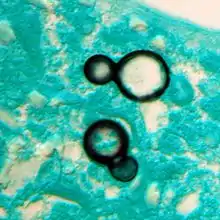

Once suspected, the diagnosis of blastomycosis can usually be confirmed by demonstration of the characteristic broad based budding organisms in sputum or tissues by KOH prep, cytology, or histology.[14] Tissue biopsy of skin or other organs may be required in order to diagnose extra-pulmonary disease. Blastomycosis is histologically associated with granulomatous nodules. Commercially available urine antigen testing appears to be quite sensitive in suggesting the diagnosis in cases where the organism is not readily detected. While culture of the organism remains the definitive diagnostic standard, its slow growing nature can lead to delays in treatment of up to several weeks. However, sometimes blood and sputum cultures may not detect blastomycosis.[15]

Granuloma with early suppuration. Fungal organisms difficult to recognize at this low magnification.

Large yeast-like fungi seen within giant cells at arrows.

Large yeast-like fungi seen within giant cells at arrows.Budding yeasts in cytoplasm of giant cells at arrows. Broad-based budding and double countoured cell wall seen in the giant cell in the center is characteristic of Blastomyces dermatitidis.